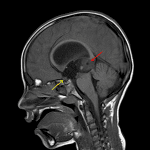

Age: 7

Sex: Male

Indication: Altered mental status

Teratoma (pineal region)